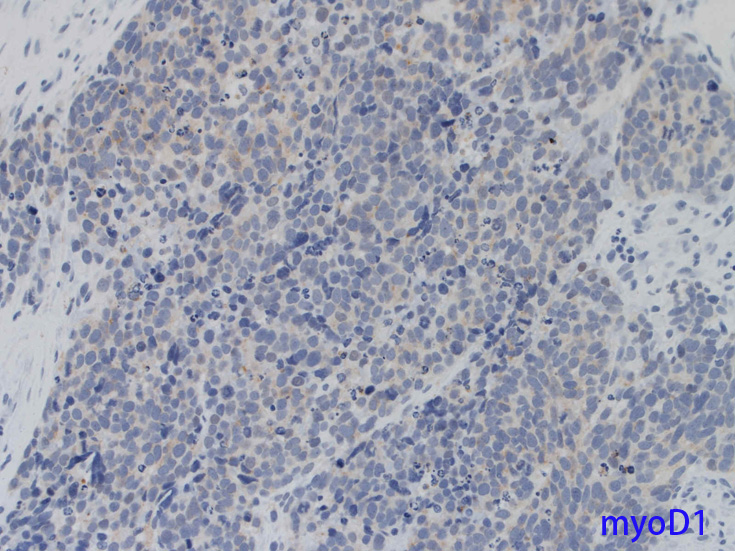

Desmin, 筋特異的アクチン(HHF-35), myoglobin, MyoD1, myoegeninなどの筋マーカはARMSでよく染色されるがES/PNETでは陰性である。

筋形成過程は多潜能未熟間葉系細胞の骨格筋へのcommitmentとdifferentiationからなりMyoD遺伝子ファミリーにより制御されている。このファミリーにはMyoD1/myf-3, myogenin/myf-4, myf-5, MRF-4遺伝子などが含まれ, 筋特異遺伝子上エンハンサー領域に結合し発現誘導の転写因子として働くDNA結合蛋白をコードしている。

骨格筋ではこれらの遺伝子発現は胚形成期に限られるためMyoDやmyogenin抗体は細胞系列の同定や他に分化や特徴のない肉腫においてrhabdomyosarcoma診断確定の目的で使われてきた。

免疫染色 筋マーカ, 神経内分泌マーカほか;本例では神経内分泌マーカがすべて陽性になっている.

myoD1.jpg

DesminmyogeninmyoD1